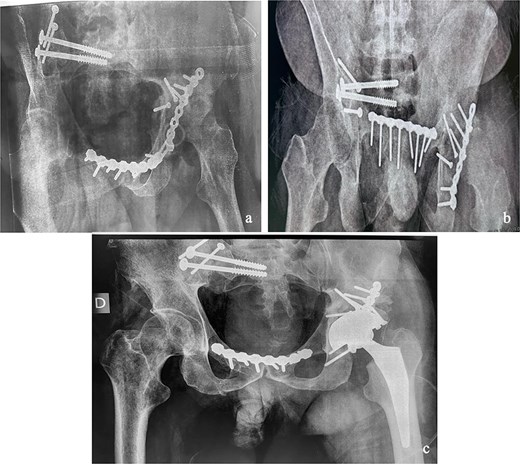

This was a 42-year-old male patient with no previous medical history who was admitted to the intensive care unit for treatment of polytrauma: severe chest trauma and pelvic trauma. During his stay in intensive care, the patient developed a pulmonary infection complicated by septicemia, requiring prolonged antibiotic therapy and thereby contraindicating any internal surgical fixation. After hemodynamic and respiratory stabilization, he was transferred to our department 40 days after the trauma with the following injuries: an unstable pelvic ring fracture classified as Tile-AO B1-2 [4]: disjunction of the pubic symphysis, disjunction of the right sacroiliac joint, and an ipsilateral crescent fracture classified as Kumar-Day 2 [5], along with a transverse–posterior wall fracture of the left acetabulum associated with a posterior dislocation of the hip, which was initially reduced but remained unstable. Fixation was performed using a Hoffmann II external fixator applied to the iliac crests with poor reduction (Fig. 1). He presented with complete weakness of the left foot dorsiflexors, with preserved sensation and no urogenital or abdominal complications. ORIF was performed in two stages, 5 days apart. The first stage consisted of performing the first two windows of the ilioinguinal approach: the lateral window to access the sacroiliac joint and the middle window to access the lower part of the sacroiliac joint and remove the osteofibrous callus. A Pfannenstiel approach was used to remove the callus at the pubic symphysis and fix it with a plate. The patient was then placed in the prone position and a posterior approach to the right sacroiliac joint was performed to carry out the same procedures on the posterior part of this joint and to perform fixation using ilioiliac and iliosacral screws. The second stage of the operation involved acetabular surgery. Given the chronic dislocation of the left hip, an anterior approach to the hip was performed to remove the intra-articular fibrosis facilitating the subsequent reduction of the femoral head. A Kocher-Langenbeck approach was then performed to remove the callus, reduce the femoral head and fracture, and fix it with a plate (Fig. 2). Postoperatively, the patient retained neurological deficits. At 6 months, the patient was able to walk without assistance and had a Harris Hip Score (HHS) score of 80 and Majeed score of 75 [6, 7].

(a) Anteroposterior pelvic X-ray showing delayed pelvic and acetabular fractures. (b) Anterior view of the pelvis on 3D section: pubic symphysis disjunction and right sacroiliac dislocation (arrows), transverse component of the left acetabular fracture (star). (c) Posterior view of the pelvis on 3D section: right crescent fracture associated with right sacroiliac dislocation (circles), fracture of the posterior wall of the left acetabulum associated with posterior dislocation of the femoral head (triangle). (d) Axial section of the pelvic CT-scan: right crescent fracture Kumar-Day 2 (green arrow).

Immediate postoperative X-rays. (a) Anteroposterior pelvic X-ray. (b) Inlet view of the pelvis. (c) Alar oblique view of the pelvis. (d) Obturator oblique view of the pelvis.